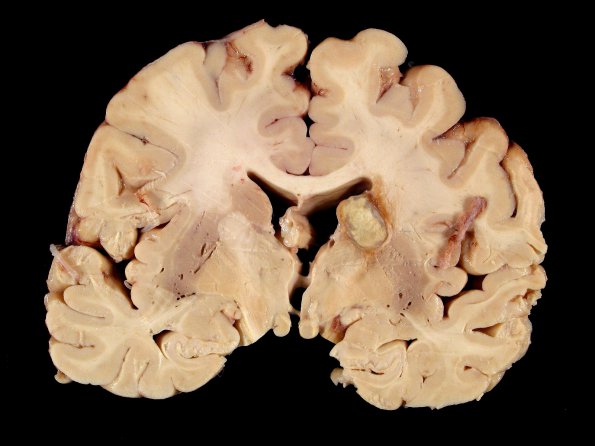

This single cryptococcoma is adjacent to the ventricle with a hyperemic rim and a collagenous wall. Notice that this lesion is not accompanied by soap bubbles elsewhere in the section.